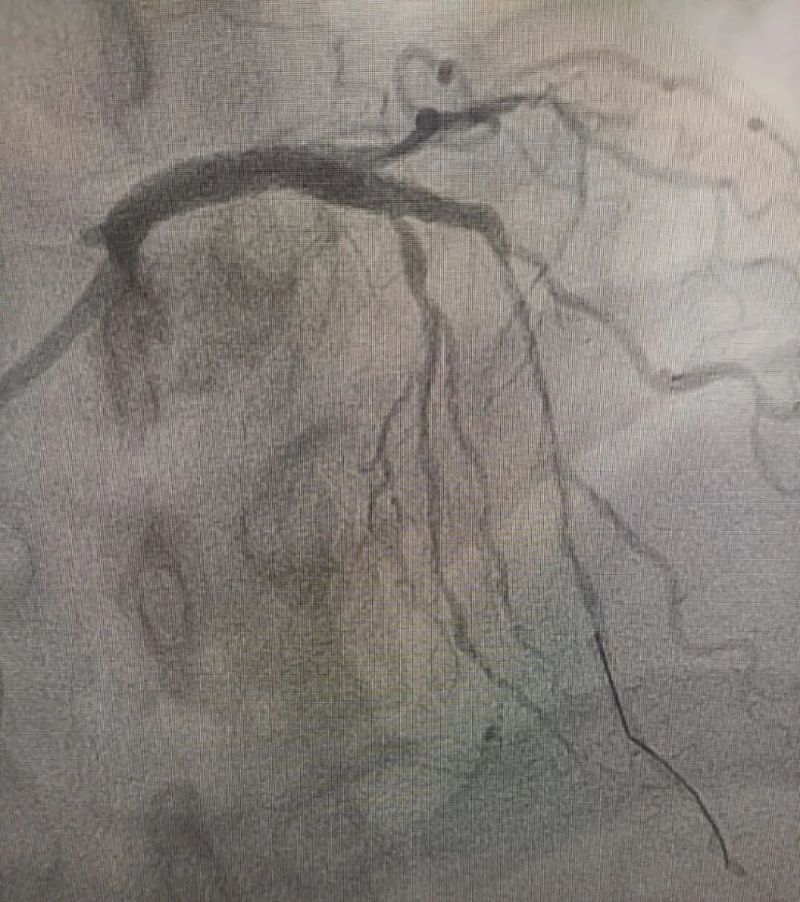

術中造影顯示,左主干至前降支近段重度狹窄——這正是導致心臟缺血、誘發室顫的“罪魁禍首”。主動脈球囊反搏植入、球囊擴張、支架植入......介入團隊精準操作,一氣呵成。堵塞的血管順利開通,血流重新涌動,這顆一度瀕臨停跳的心臟終于重獲生機。

冠狀動脈造影圖

術前 (左主干至前降支近段重度狹窄)

術后(左主干至前降支近段原狹窄消失)